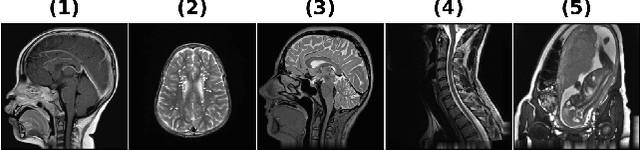

Abstract:Regularization plays a crucial role in reliably utilizing imaging systems for scientific and medical investigations. It helps to stabilize the process of computationally undoing any degradation caused by physical limitations of the imaging process. In the past decades, total variation regularization, especially second-order total variation (TV-2) regularization played a dominant role in the literature. Two forms of generalizations, namely Hessian-Schatten norm (HSN) regularization, and total generalized variation (TGV) regularization, have been recently proposed and have become significant developments in the area of regularization for imaging inverse problems owing to their performance. Here, we develop a novel regularization for image recovery that combines the strengths of these well-known forms. We achieve this by restricting the maximization space in the dual form of HSN in the same way that TGV is obtained from TV-2. We name the new regularization as the generalized Hessian-Schatten norm regularization (GHSN), and we develop a novel optimization method for image reconstruction using the new form of regularization based on the well-known framework called alternating direction method of multipliers (ADMM). We demonstrate the strength of the GHSN using some reconstruction examples.